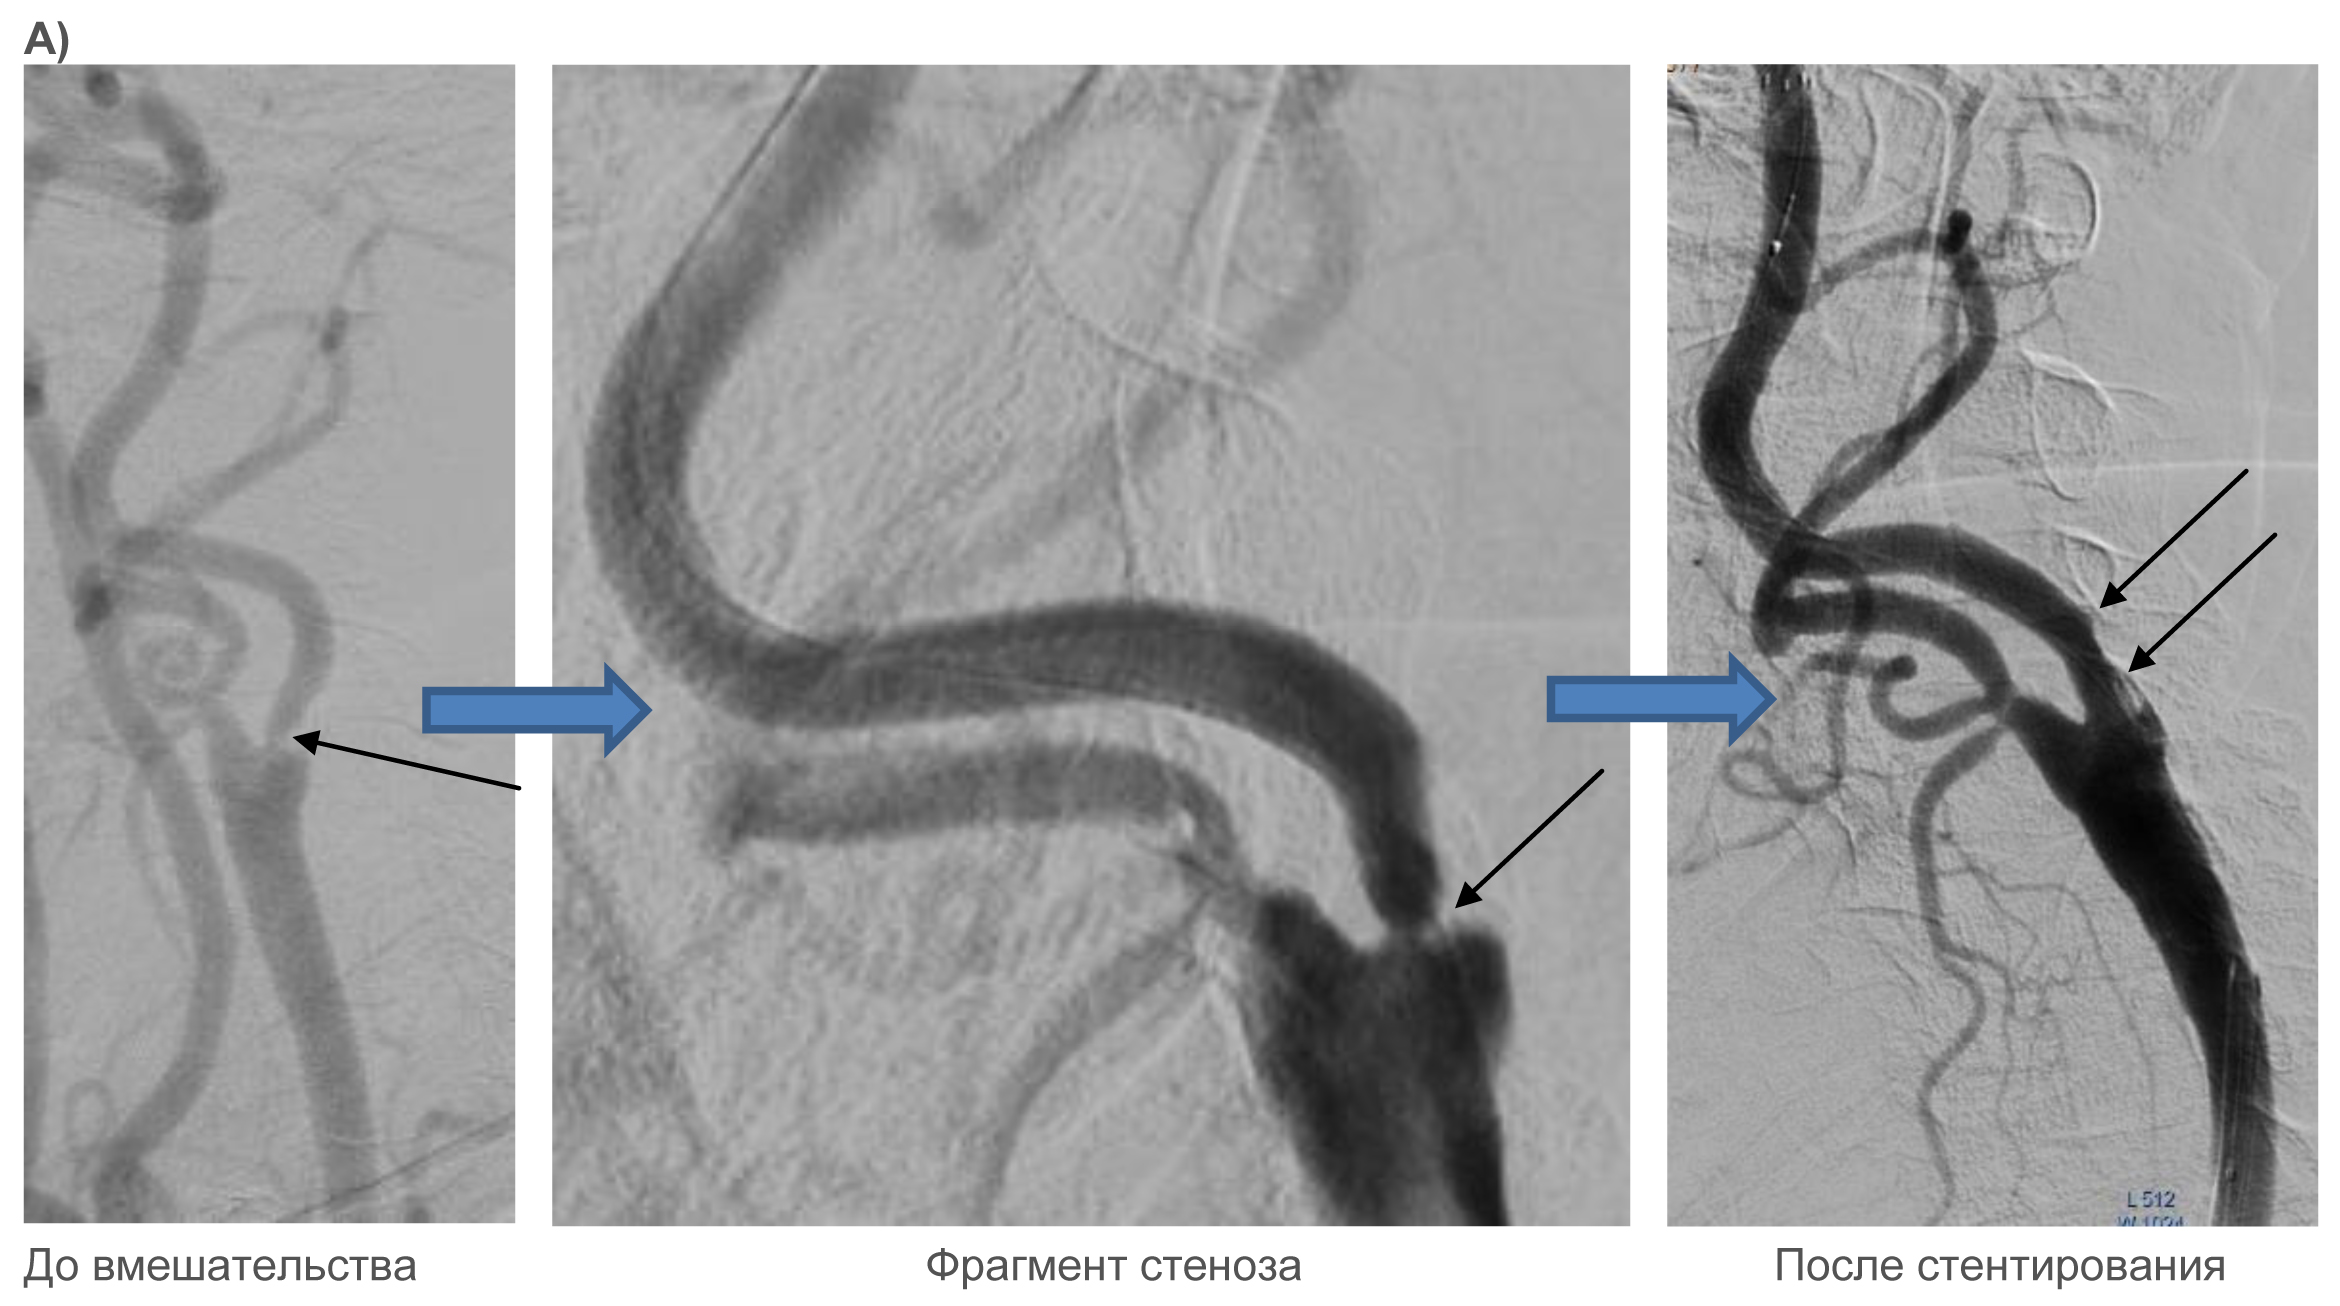

История болезни атеросклероз стеноз сонных артерий - фото презентация